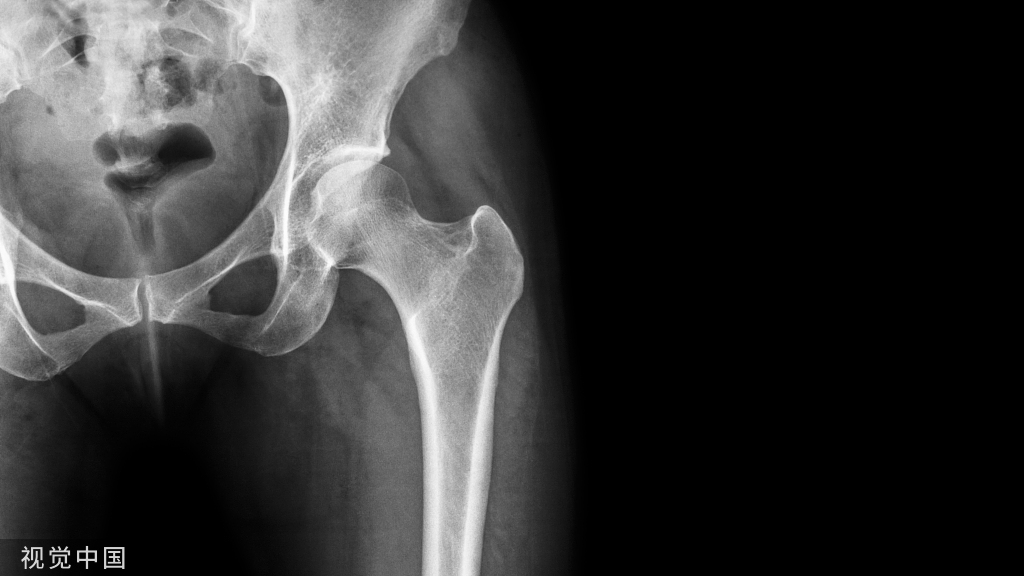

图1股骨远端骨折示例。沿股骨远端骨块作一中轴线,骨折线与中轴线相交,形成2锐角(Acute angles)。

病例2 股骨远端骨折的Poller钉置入方法。